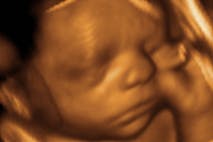

Dear PBS, I don’t think there’s a compassionate way to murder infants